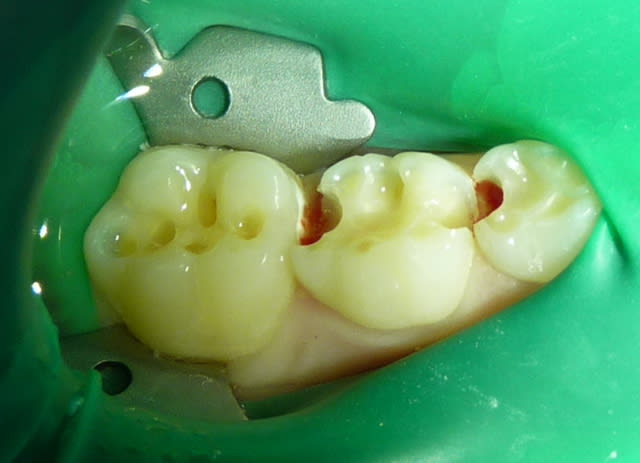

tes photos sont excellentes!

Il faut toujours essayer : parfois on est un peu sous gingival , ça à l'air mal barré et puis on met la digue et hop : magie !!! cf photo ci-joint.

Digue si6cja - Eugenol